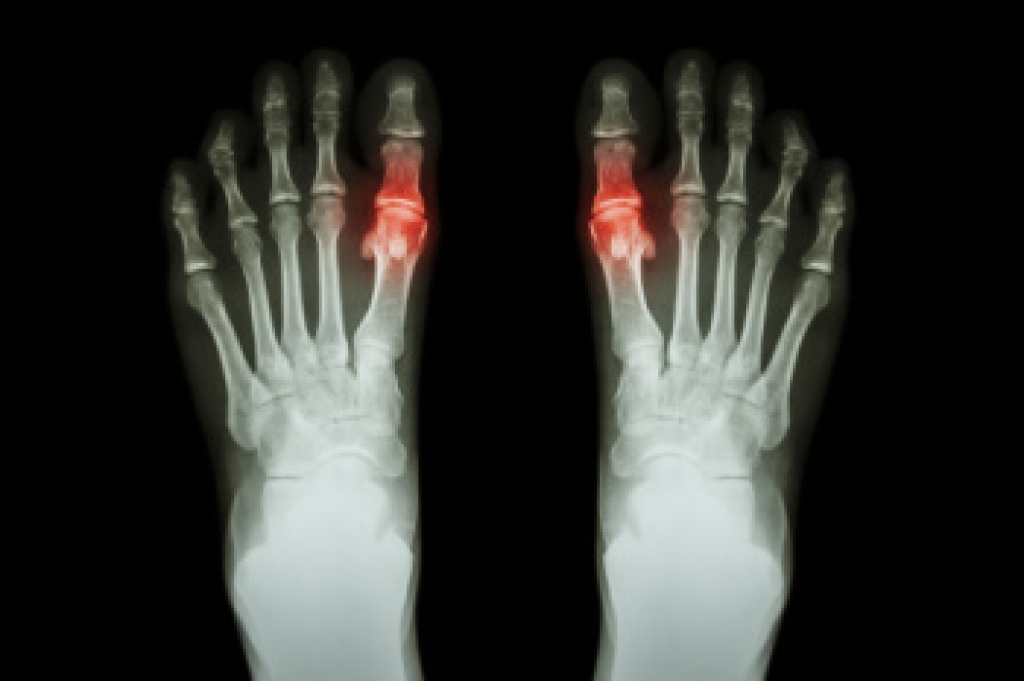

Systemic diseases affect the whole body, and symptoms usually are displayed in the feet. This condition can make a patient’s ability to walk unbearable. Systemic diseases include gout, diabetes mellitus, neurological disorders, and arthritis.

Gout – is caused by an excess of uric acid in the body. Common symptoms include pain, inflammation, and redness at the metatarsal/phalangeal joint of the base big toe. Gout can be treated by NSAIDs to relieve pain and inflammation, and other drugs that lower the acid levels in the body.